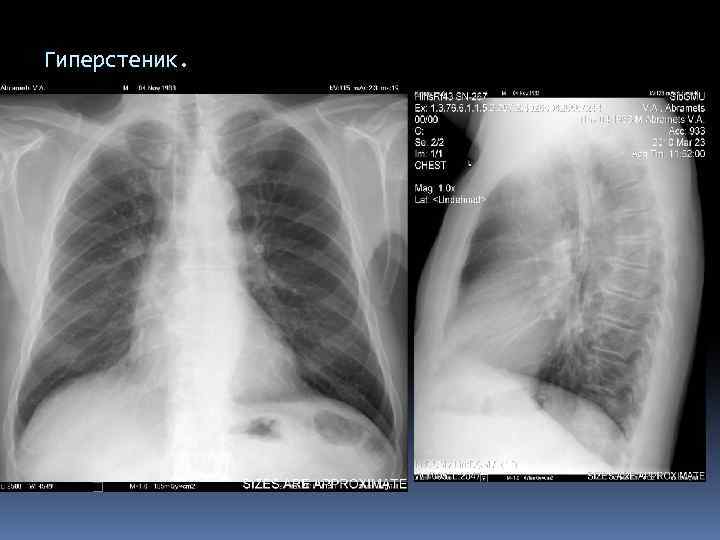

Гиперстеник.

Гиперстеник. Конфигурация ССС.